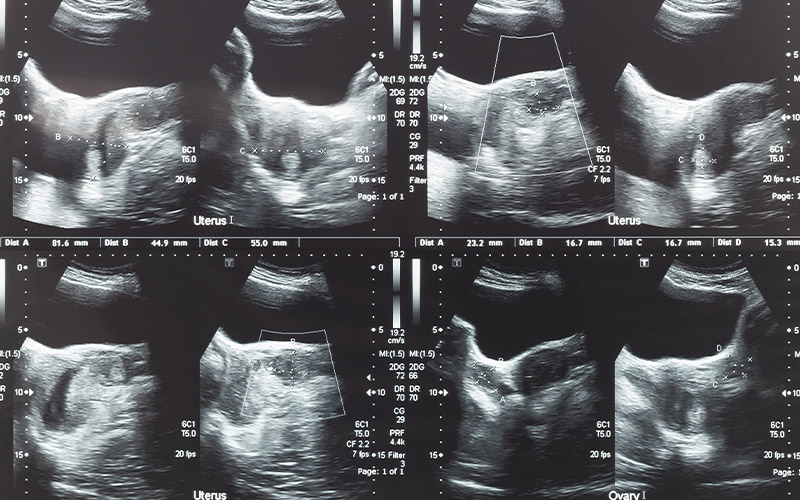

For gynecologic cancers—cancers that start in the female reproductive organs—it is important to pay attention to symptoms and seek regular care from an OB/GYN.

Different types of gynecologic cancers may be treated in different ways, and we rely on a range of advanced therapies to meet your individual needs, including surgery, radiation and chemotherapy. At your first visit, your doctor will review your medical history, imaging and lab results, and pathology reports. Your doctor will also perform a physical exam and a pelvic exam. Using all this information, your doctor will put together a personalized treatment plan that takes into consideration your lifestyle and future plans while treating your gynecologic cancer as effectively as possible.